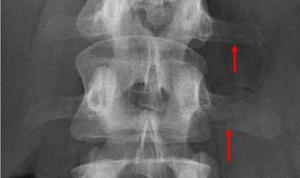

Рентгенография является стандартным методом визуализации для диагностики травм позвоночника. Антеропостериорные и боковые проекции поясничного и грудного отделов обычно являются минимально необходимыми исследованиями. Компьютерная томография (КТ) представляет собой незаменимый инструмент для оценки сложности повреждений позвонков, которые могут быть видны на рентгенограммах, а также для выявления более мелких переломов, которые сложно обнаружить на обычных рентгеновских снимках. Магнитно-резонансная томография (МРТ) требуется в случаях, когда пациент сообщает о потерях чувствительности.

Для более точной диагностики используются различные методы визуализации. Наиболее распространенными являются:

- Рентгенография: Это первый и наиболее доступный метод, который позволяет выявить наличие перелома и оценить его степень. На рентгеновских снимках можно увидеть изменения в форме позвонка, а также наличие смещения.

- Компьютерная томография (КТ): Этот метод предоставляет более детальную информацию о состоянии позвонков и окружающих тканей. КТ позволяет выявить мелкие трещины и оценить степень компрессии позвонка.